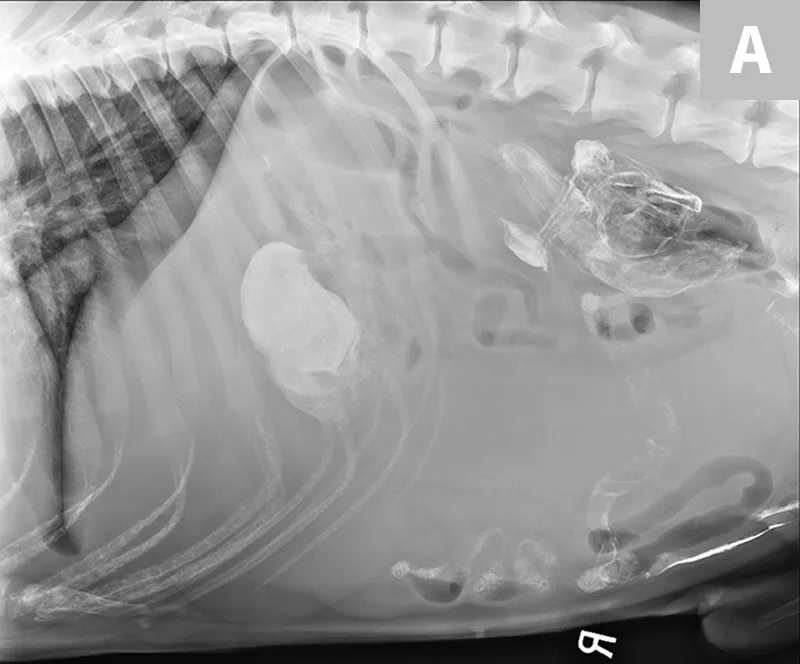

Treatment of the underlying disease in these conditions may relieve or reduce splenomegaly. In cases of splenic torsion (Figures 5 and 6), splenectomy is the recommended treatment, with approximately 90% of dogs surviving to discharge.19

FIGURE 5

Splenic torsion appears as a large soft-tissue opacity that displaces the GI tract caudally and peripherally (A). The splenic head is obscured caudal to the left margin of the stomach (B). The metallic opacity seen in the stomach and intestines is caused by recent barium administration.